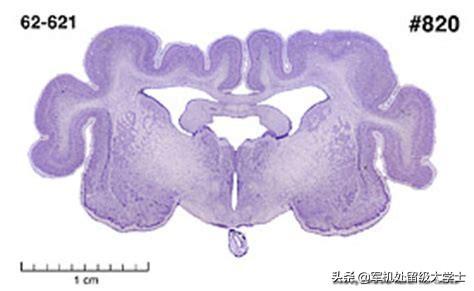

この写真がモルモットの大きさを物語っている。